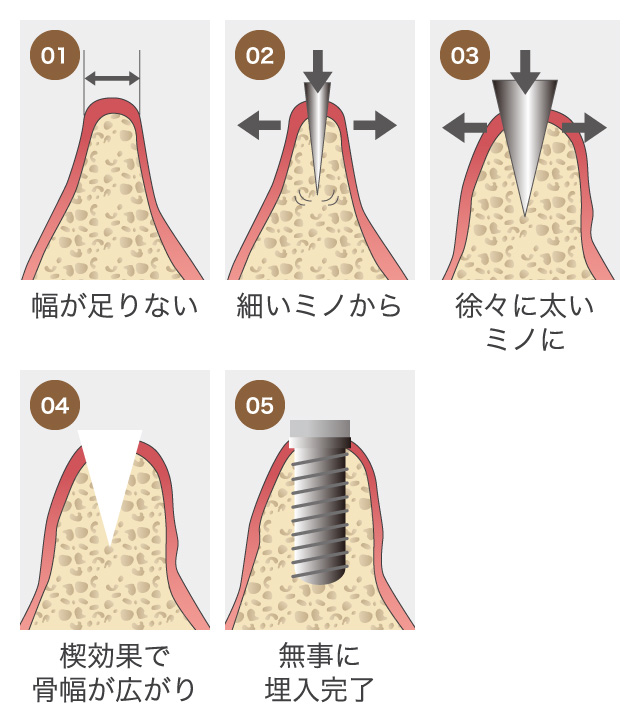

インプラント治療とは術前診査・診断を十分に行った上で、歯が抜けてしまった部分にインプラント(人工歯根)を埋め込み、その上から自然な見た目の人工歯を装着させるという治療法で、骨にしっかりとインプラント(人工歯)を定着させるため、自分の歯のようにしっかり、思い切り噛めるようになります。